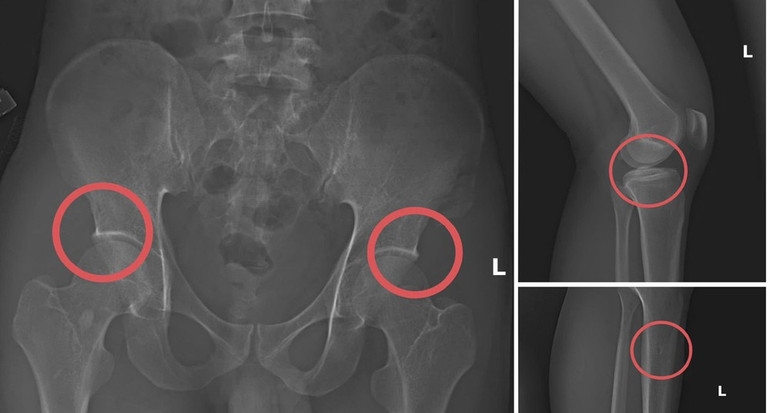

Lợi dụng thời gian dài công tác trong ngành và am hiểu cấu trúc xương, khớp, Châu đã xây dựng quy trình trục lợi theo chuỗi khép kín gồm: Vận động người mua bảo hiểm nhân thọ, trực tiếp gây thương tích bằng thuốc mê và các dụng cụ tác động lực, sau đó dựng hiện trường giả để hợp thức hóa hồ sơ điều trị.

Đáng chú ý, Châu trực tiếp thực hiện hành vi tiêm thuốc mê rồi dùng kim tiêm, búa để tác động vào xương người mua bảo hiểm, tạo nên các vết vỡ xương tương tự tai nạn thật. Khi thương tích đã tạo xong, Châu tiếp tục hướng dẫn các đối tượng dựng hiện trường giả như điện giật ngã, trượt chân ngã suối nhằm hợp thức hóa bệnh án và hoàn thiện hồ sơ yêu cầu chi trả.